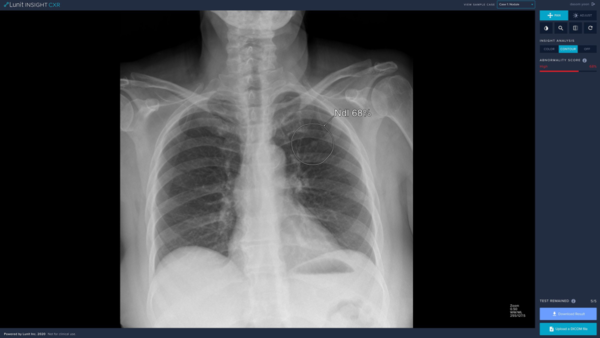

이번 허가를 받은 '루닛 인사이트 CXR 3'은 2018년 허가 받은 '루닛 인사이트 CXR', 2019년 허가 받은 '루닛 인사이트 CXR 2'의 업그레이드 버전이다. 루닛의 독자적인 인공지능 기술을 바탕으로 환자의 흉부 엑스레이 사진을 분석해 폐 결절 및 종괴, 기흉, 흉막삼출, 무기폐, 기복증, 폐 경화 등의 주요 폐 비정상 소견을 97%의 정확도로 검출해낸다.

루닛 인사이트 CXR 3에는 9가지 종류의 병변을 찾을 수 있는 기술이 탑재돼 있다. 폐 결절, 폐 경화, 기흉 등을 동시에 검출할 수 있어, 흉부 엑스레이에서 주요 폐 질환을 빠르고 정확하게 판독하는 데 도움이 될 것으로 기대된다. 다양한 폐 질환을 보다 빠르고 정확하게 진단하기 위해 지속적으로 제품의 알고리즘 성능 발전이 필요한 이유다.